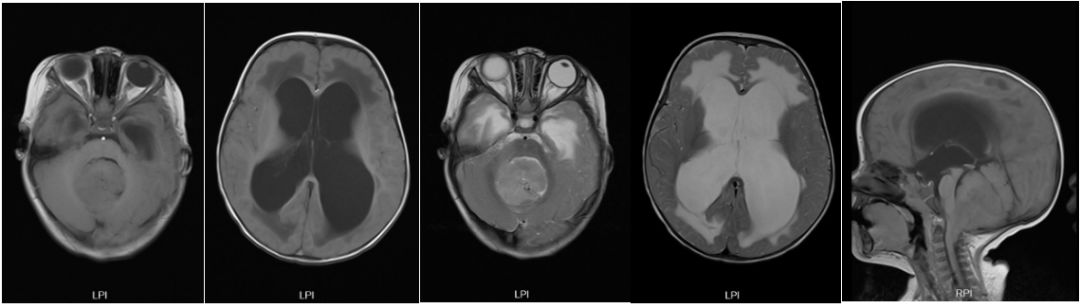

浙江大学医学院附属儿童医院门诊头颅磁共振提示:后颅窝占位,梗阻性脑积水。

图1. 头颅MR平扫:a,b为T1加权像,c,d为T2加权像,e为矢状位T1。见后颅窝巨大实性均质肿块,伴幕上严重脑积水。